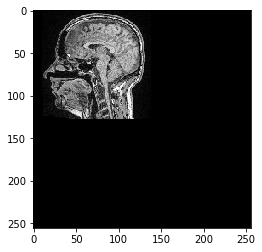

Ahora definimos una transformación afín usando scikit-image y la aplicamos a la imagen.

from skimage import transform as tf

# define transform with #scikit image

transform = tf.AffineTransform(scale=0.5, translation=[10,0])

transformed_image = tf.warp(image, transform.inverse)

imshow(transformed_image)

<matplotlib.image.AxesImage at 0x25a6edb8d60>

../_images/ee46efb712e6a7f00d1c03698e27693eb7310b59b6c954469d8c2960bfca3103.png